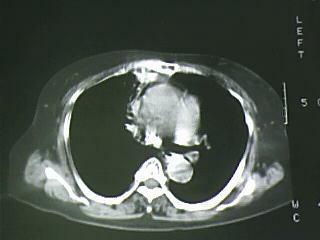

以下是引用bmw011在2009-4-14 19:14:00的发言:[br]右肺继发型肺结核---纵隔淋巴结多发钙化----左肺支扩。支持

以下是引用杀毒软件在2009-4-14 17:52:00的发言:[br]考虑---右肺继发型肺结核---纵隔淋巴结多发钙化----左肺支扩

以下是引用黑白光影在2009-4-14 20:36:00的发言:[br]右肺继发型肺结核;左下慢性支气管炎性病变。